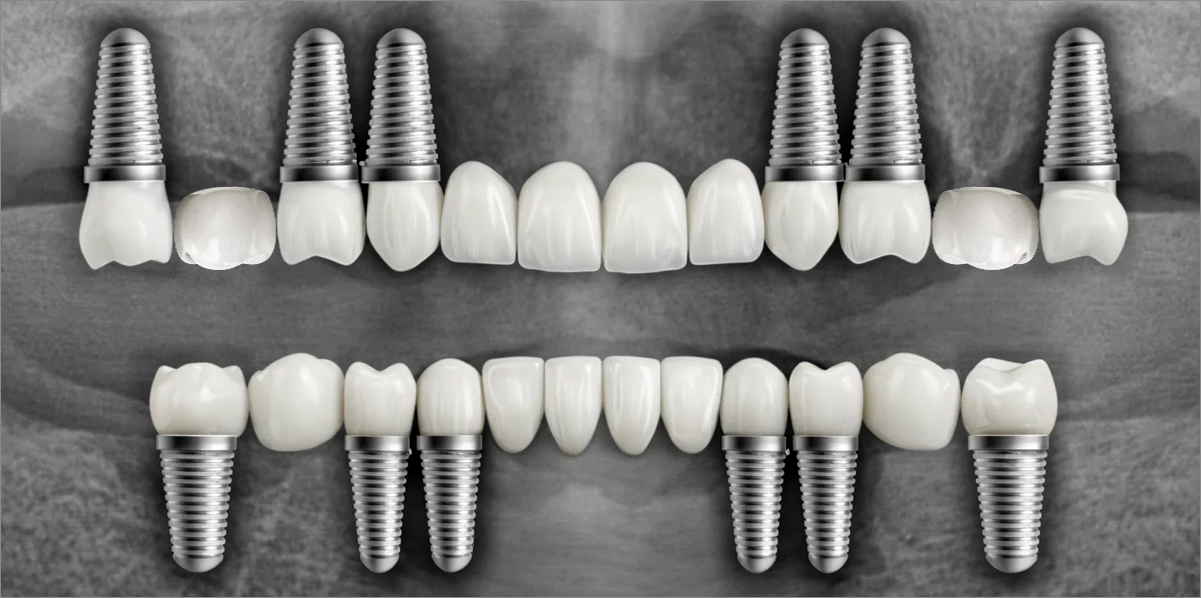

Full Placement

Using a method of placing 8–9 implants in the maxilla and 8 implants in the mandible, this approach fully restores all 28 natural teeth, creating an oral environment most closely resembling

natural dentition.

Minimal Placement

Using a method of placing 6–7 implants in the maxilla and 6 in the mandible, this approach restores both posterior and anterior teeth, efficiently rehabilitating the entire oral cavity.